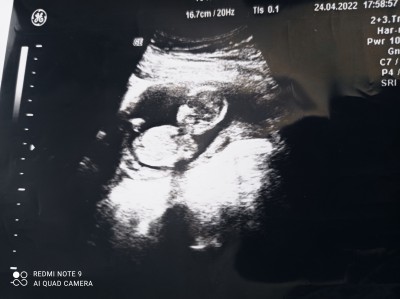

Gebelik haftası 15+3

Kız veya erkek olduğu bu şekilde nerden anlaşılıyor pipi yada vajina göremiyorum ben

12 haftalıkken ulrtasyonla bosluk goruyorum kıza benzettım  dedı. 16+5 günlüüken kontrolum vardı gttım  ulrtasyonda  oglan oldugunu ogrendık canım  yani pipisini gördük   duz yattgı ıcın bellı olmuyor senınkı

12+4 haftalikken doktorum kıza benzetti dün gittimde 17+0 kesin kız dedi çok şükür bi sıkıntımız yok değişme ihtimali de yok çok emindi çünkü biz de gördük bacak arasını

Bu gün doktora gittim kızım olacakmış çok mutluyum kız diyenler doğru tahmin etmişler rabbim sağ salim kucağıma almayı nasip etsin bana ve herkese